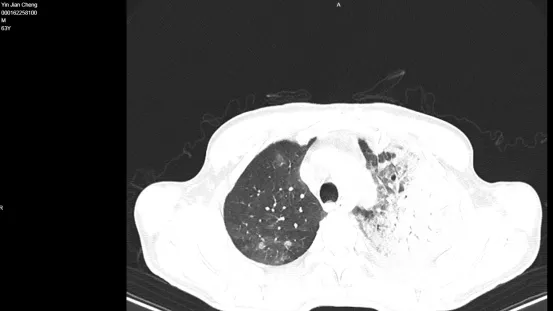

3月31日肺部CT

ICU护士接到呼吸与危重症电话急会诊并通知刘东海主治医师,刘东海医师迅速到达16楼,查看病人,端坐位,面色潮红,呼吸非常窘迫,心电监护示:心率156bpm,RR40bpm,指脉氧70%(面罩),听诊左肺呼吸音微弱,查阅肺部影像学左肺大片实变,高热,炎症指标高,肝功能异常,低蛋白血症,凝血功能异常,氧分压及氧合指数极差。 结合临床征象,影像学及检验考虑中度ARDS,重症肺炎,合并多器官功能障碍,并与家属(儿子)告知病情,短期内左肺不明原因大白肺,需详细一边检查一边治疗,建议立即转重症医学科进一步抢救诊治。